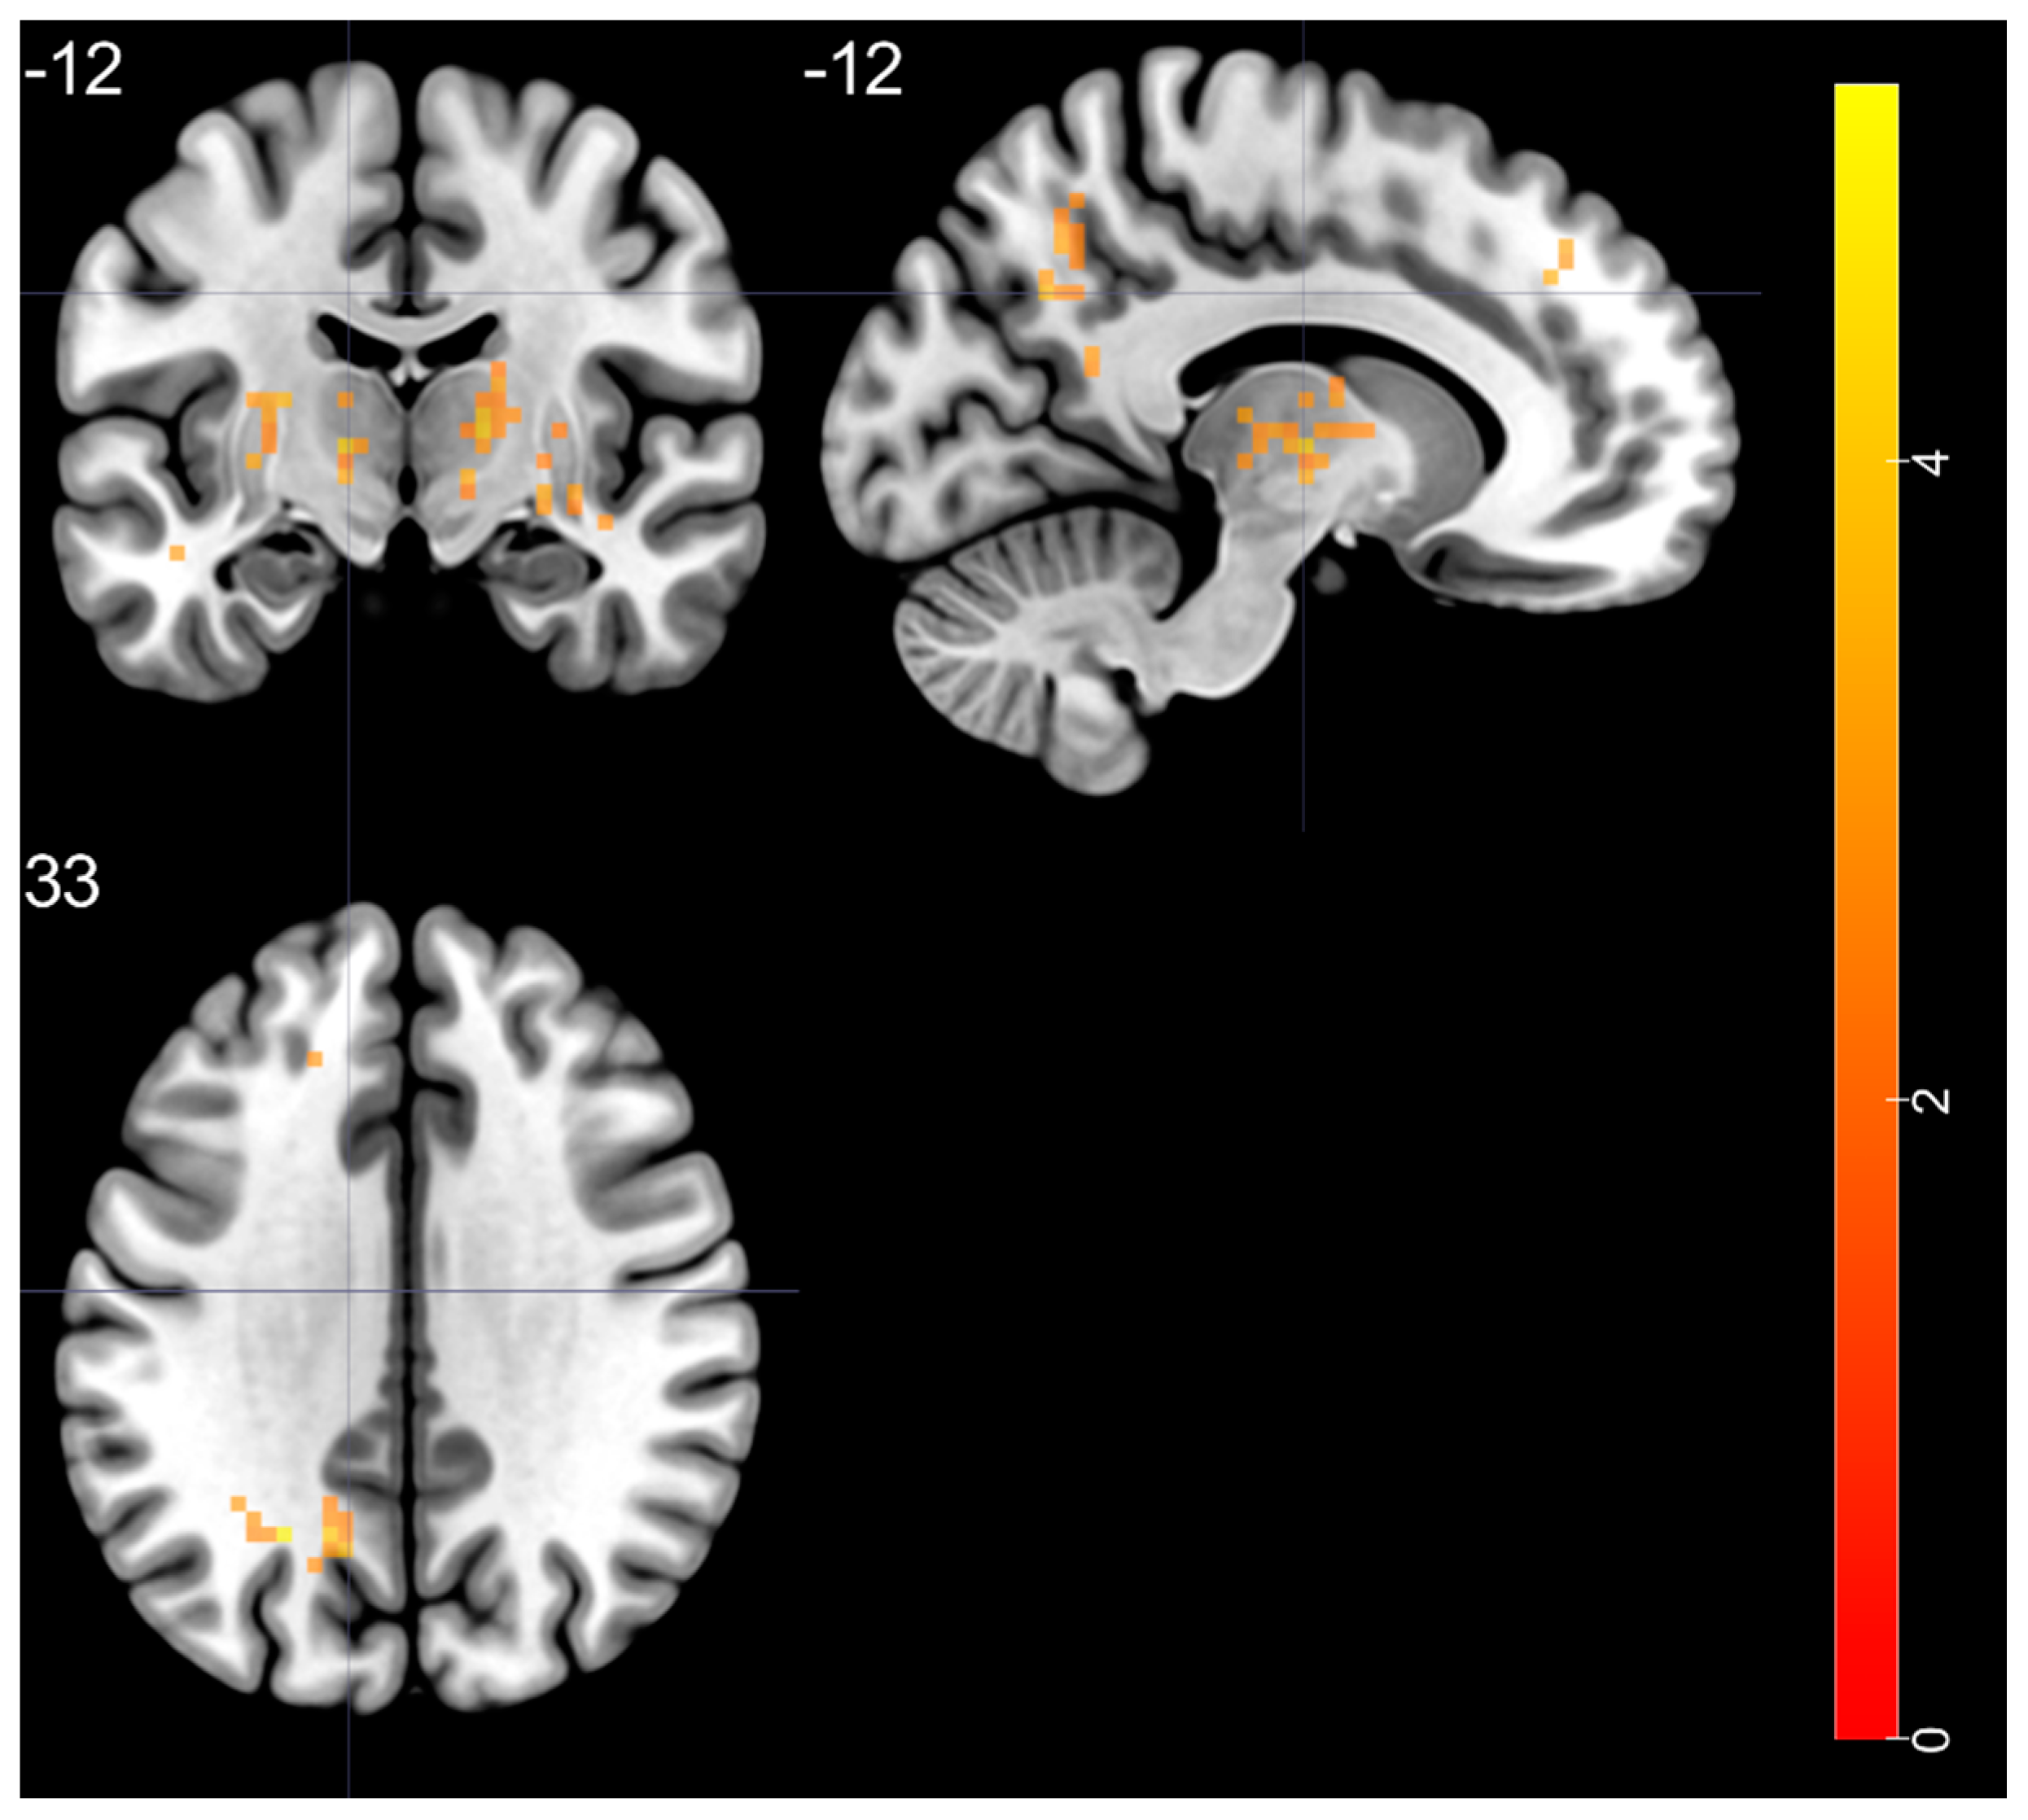

3.6. ReHo: BD vs. HC

| Brain Regions | Peak T-Scores | MNI Coordinates | Cluster Size (Voxels) | ||

|---|---|---|---|---|---|

| x | y | z | |||

| BD > HC | |||||

| left STG—BA 20 | 4.525 | −48 | −24 | −6 | 38 |

| right putamen—BA 48 | 5.178 | 33 | −6 | 0 | 144 |

| right thalamus (ventral lateral nucleus) | 4.28 | 15 | −12 | 6 | 67 |

| left thalamus (ventral lateral nucleus) | 4.351 | −12 | −12 | 3 | 113 |

| left MOG—BA 19 | 5.075 | −24 | −60 | 33 | 58 |

| left SFG—BA 9 | 3.741 | −9 | 42 | 39 | 27 |